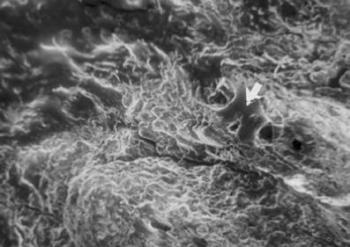

40. ábra. A csonttaraj felületén néhol még felismerhető a porcmaradvány (nyíl). SEM 400× nagyítás